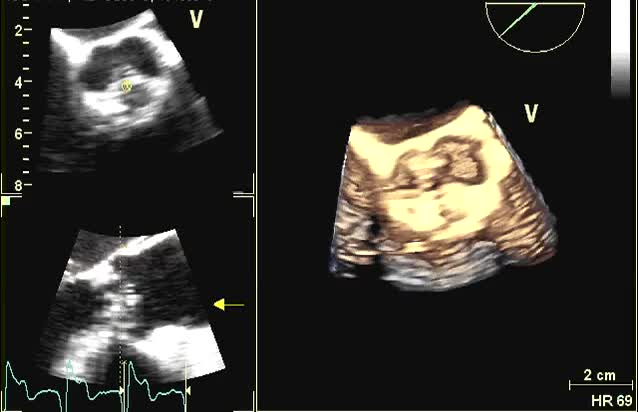

Vegetazioni aortiche